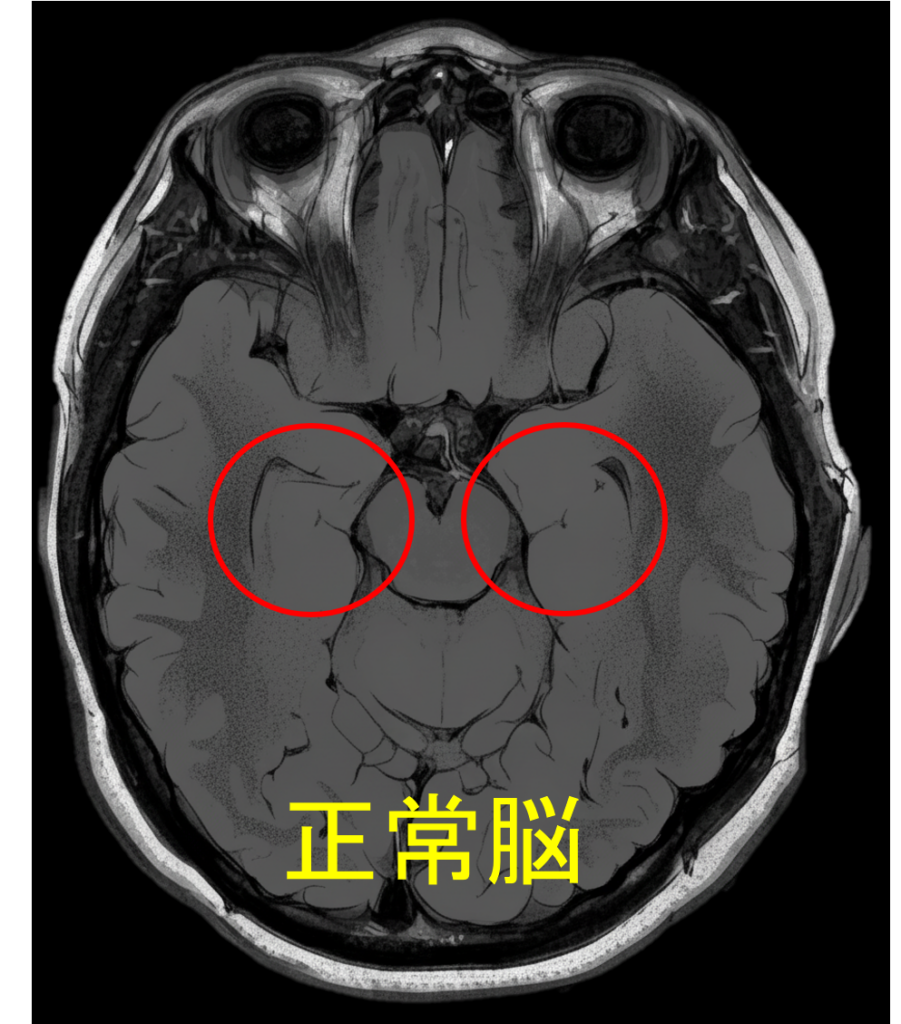

脳萎縮のMRI診断:専門医による評価の視点と検査

MRI検査は、脳の萎縮状態を客観的に確認するために不可欠です。専門医は以下の点を複合的に観察し、萎縮のタイプと原因を推測します。当院では当日MRI検査が可能です。

萎縮の場所とパターンから病態を特定する視点

- 海馬周辺の萎縮: アルツハイマー型認知症の初期に強く現れる萎縮パターン。

- 脳全体・脳室の拡大: 加齢やアルコール多飲、または血管性障害による広範囲な萎縮。脳室の拡大も確認される。

- 脳溝の広がり: 脳の溝(脳溝)が深く広がっているかを確認。

海馬に萎縮はみられない

脳溝は深く広がっている